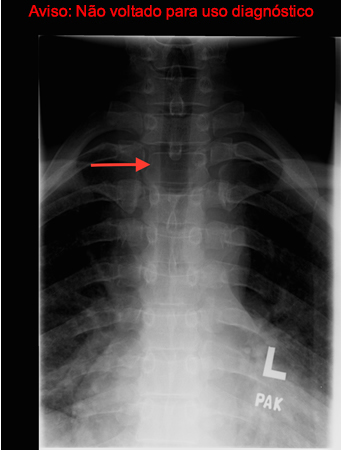

- radiografia simples das articulações sacroilíacas:

erosão da articulação sacroilíaca (quadratura de vértebras lombares) e estenose e fusão posteriormente (coluna em bambu) são sugestivas de espondilite anquilosante

- radiografia torácica:

normal; linfadenopatia mediastinal; doença pulmonar intersticial; derrame pericárdico